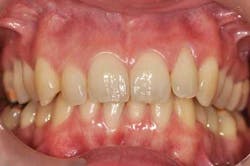

Twelve months after initial therapy, the patient’s plaque control is excellent and she no longer reports tooth mobility or gingival bleeding.

Fig. 3: 12 months after initial therapy

Tooth No. 4, because of its excessive bone loss, is further investigated. Probing is now normal (1.5 mm) — no bleeding, which indicates a gingival reattachment. This particular tooth mobility has improved from 4 to 2.